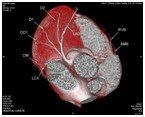

心脏大血管CT成像

冠状动脉CT成像